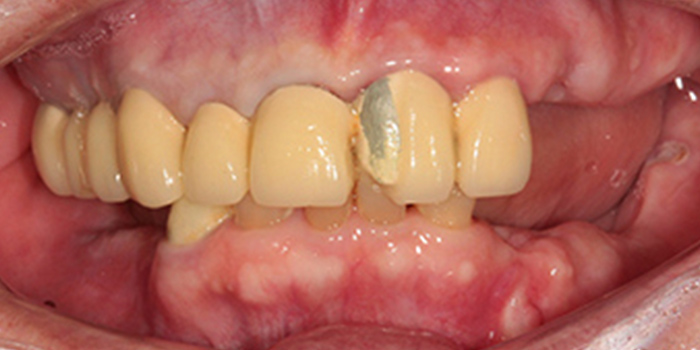

01 50대 만성치주염 남성, 앞니 심미적 개선, 저작 기능의 회복. 치료기간 6개월 -

02 50대 만성치주염 남성, 앞니 심미적 개선, 저작 기능의 회복. 치료기간 6개월 -